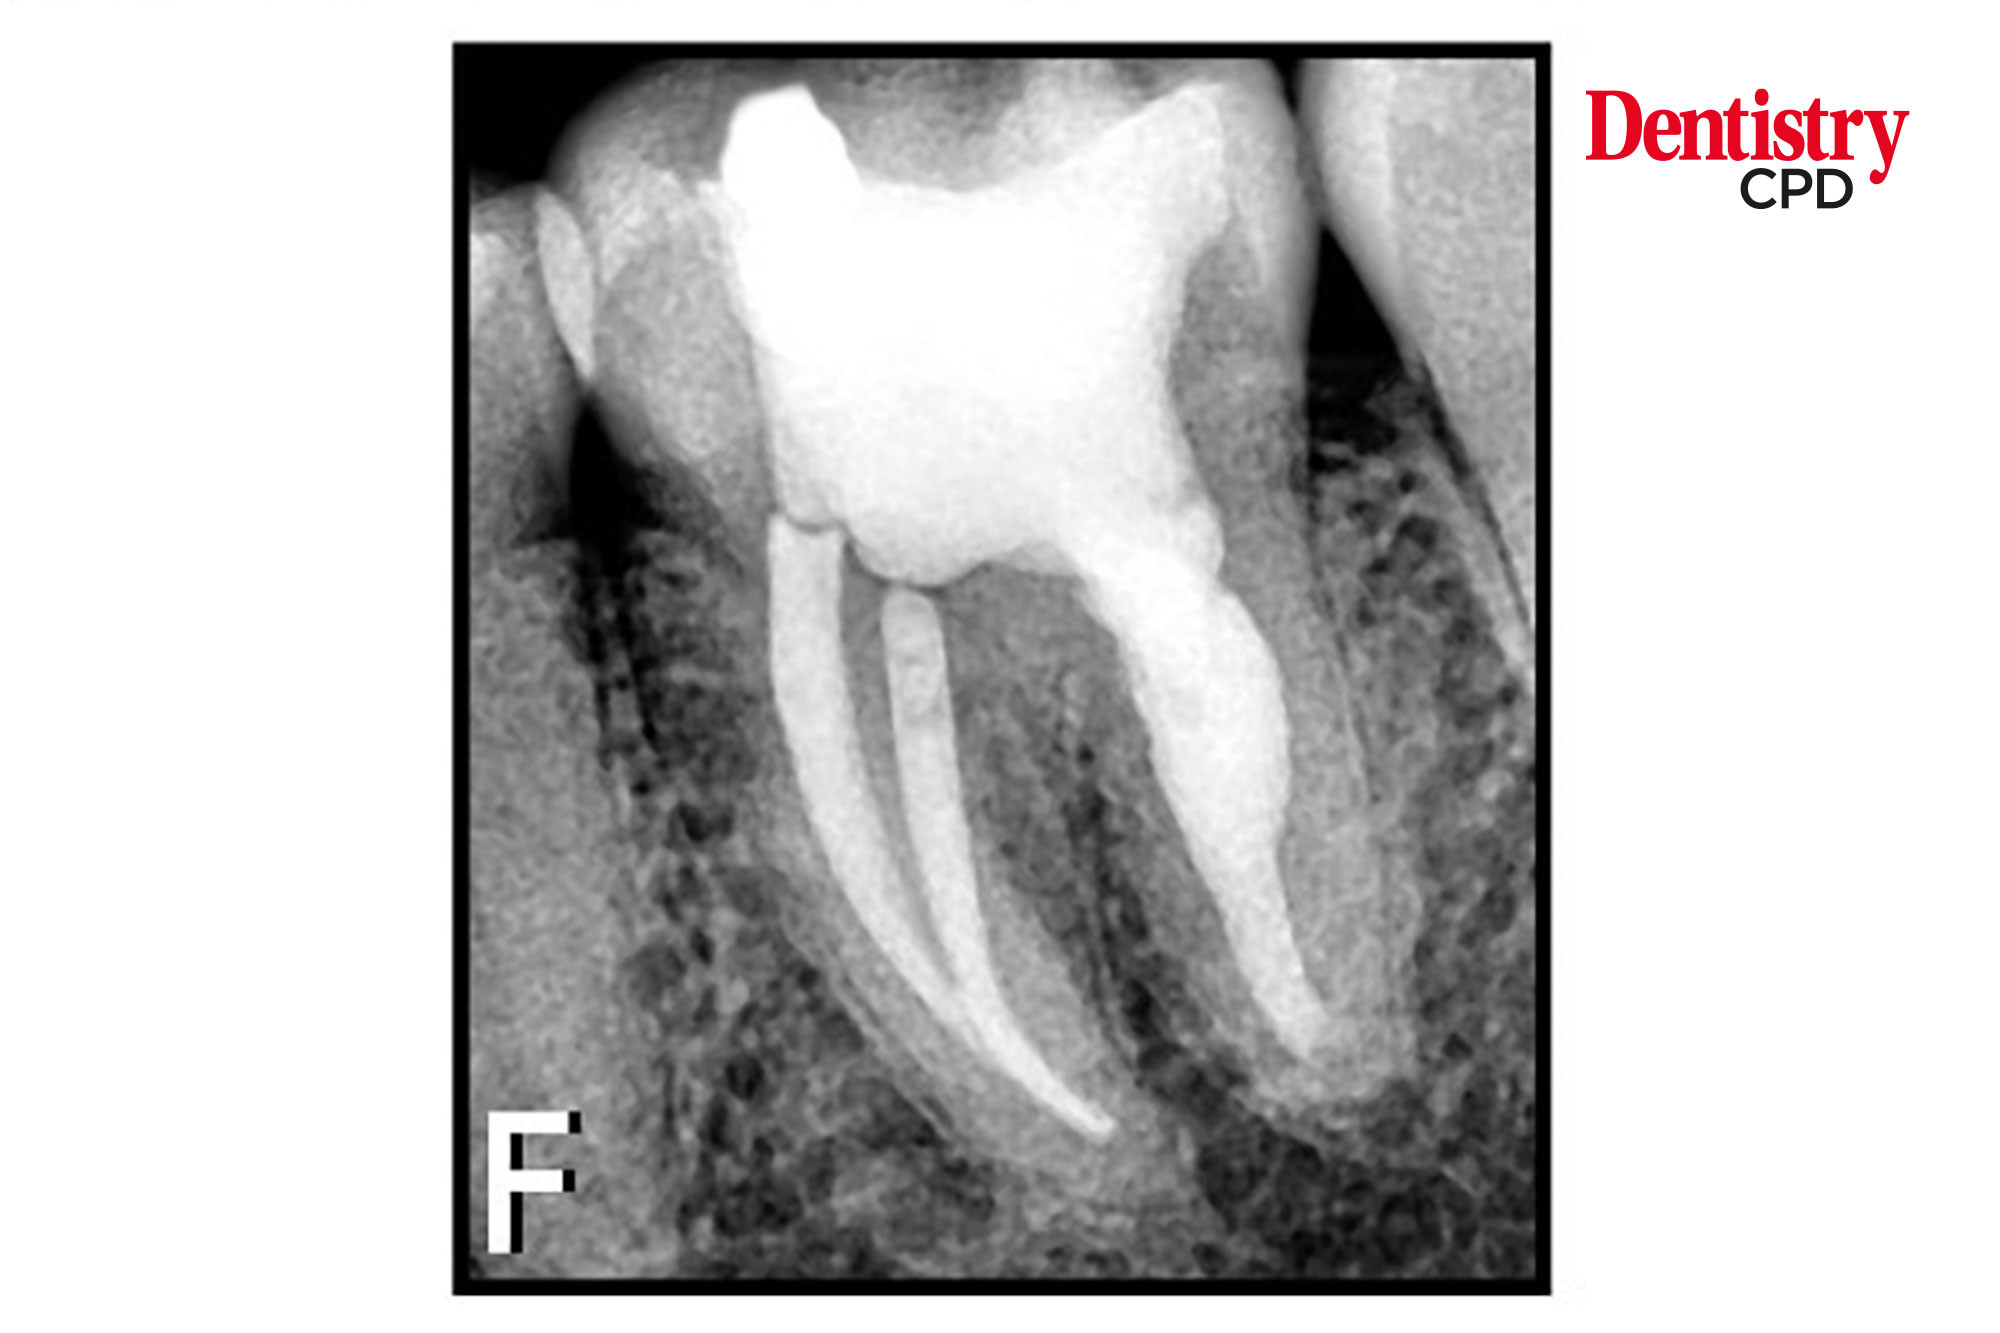

Extensive internal root resorption

This article aims to report the endodontic management of a case of extensive internal root resorption affecting a symptomatic left mandibular first molar.